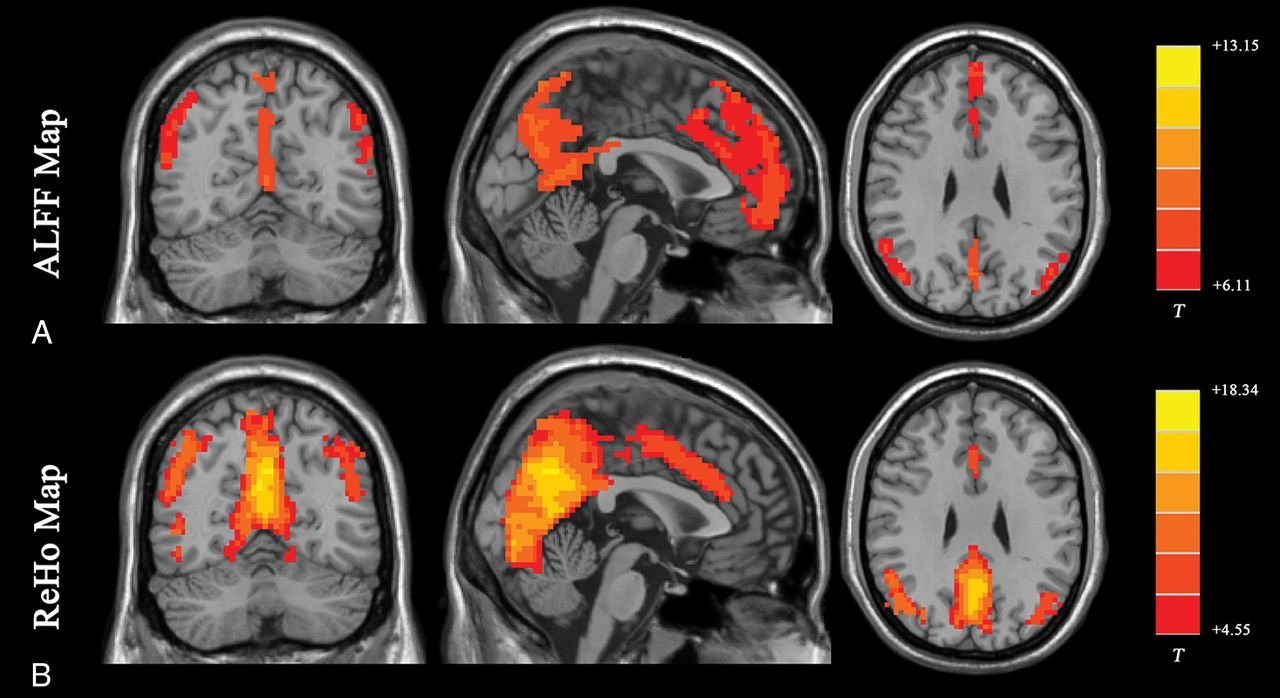

During an fMRI scan, the patient lies inside an MRI machine and performs specific tasks such as speaking, moving a limb, or responding to visual cues. The scanner records changes in blood flow associated with these activities, creating detailed maps of functional brain areas. These maps allow doctors to identify which parts of the brain are responsible for specific functions and how they may be affected by disease.